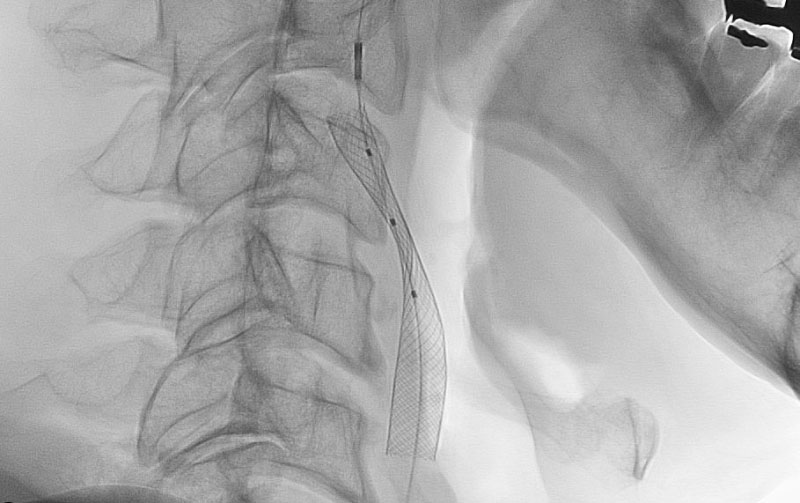

1619

'26年3月11日

左内頚動脈狭窄症

70代

大阪府の病院

手術写真

治療

前